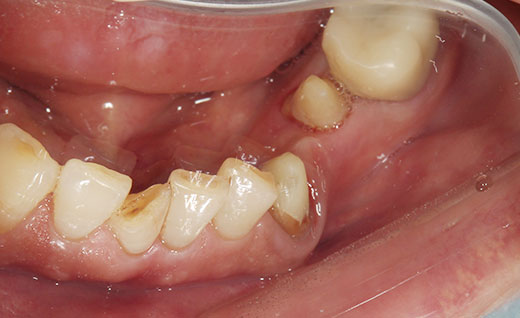

施術後

施術後です。ジルコニアは強度も強く奥歯にはおすすめです。また色味もまわりの歯に合わせて合わすことができるので比較しても新しくつけたものであることもわからないくらいの仕上がりとなります。今回のようにわざと少し汚れたような色味にすることも可能となります。